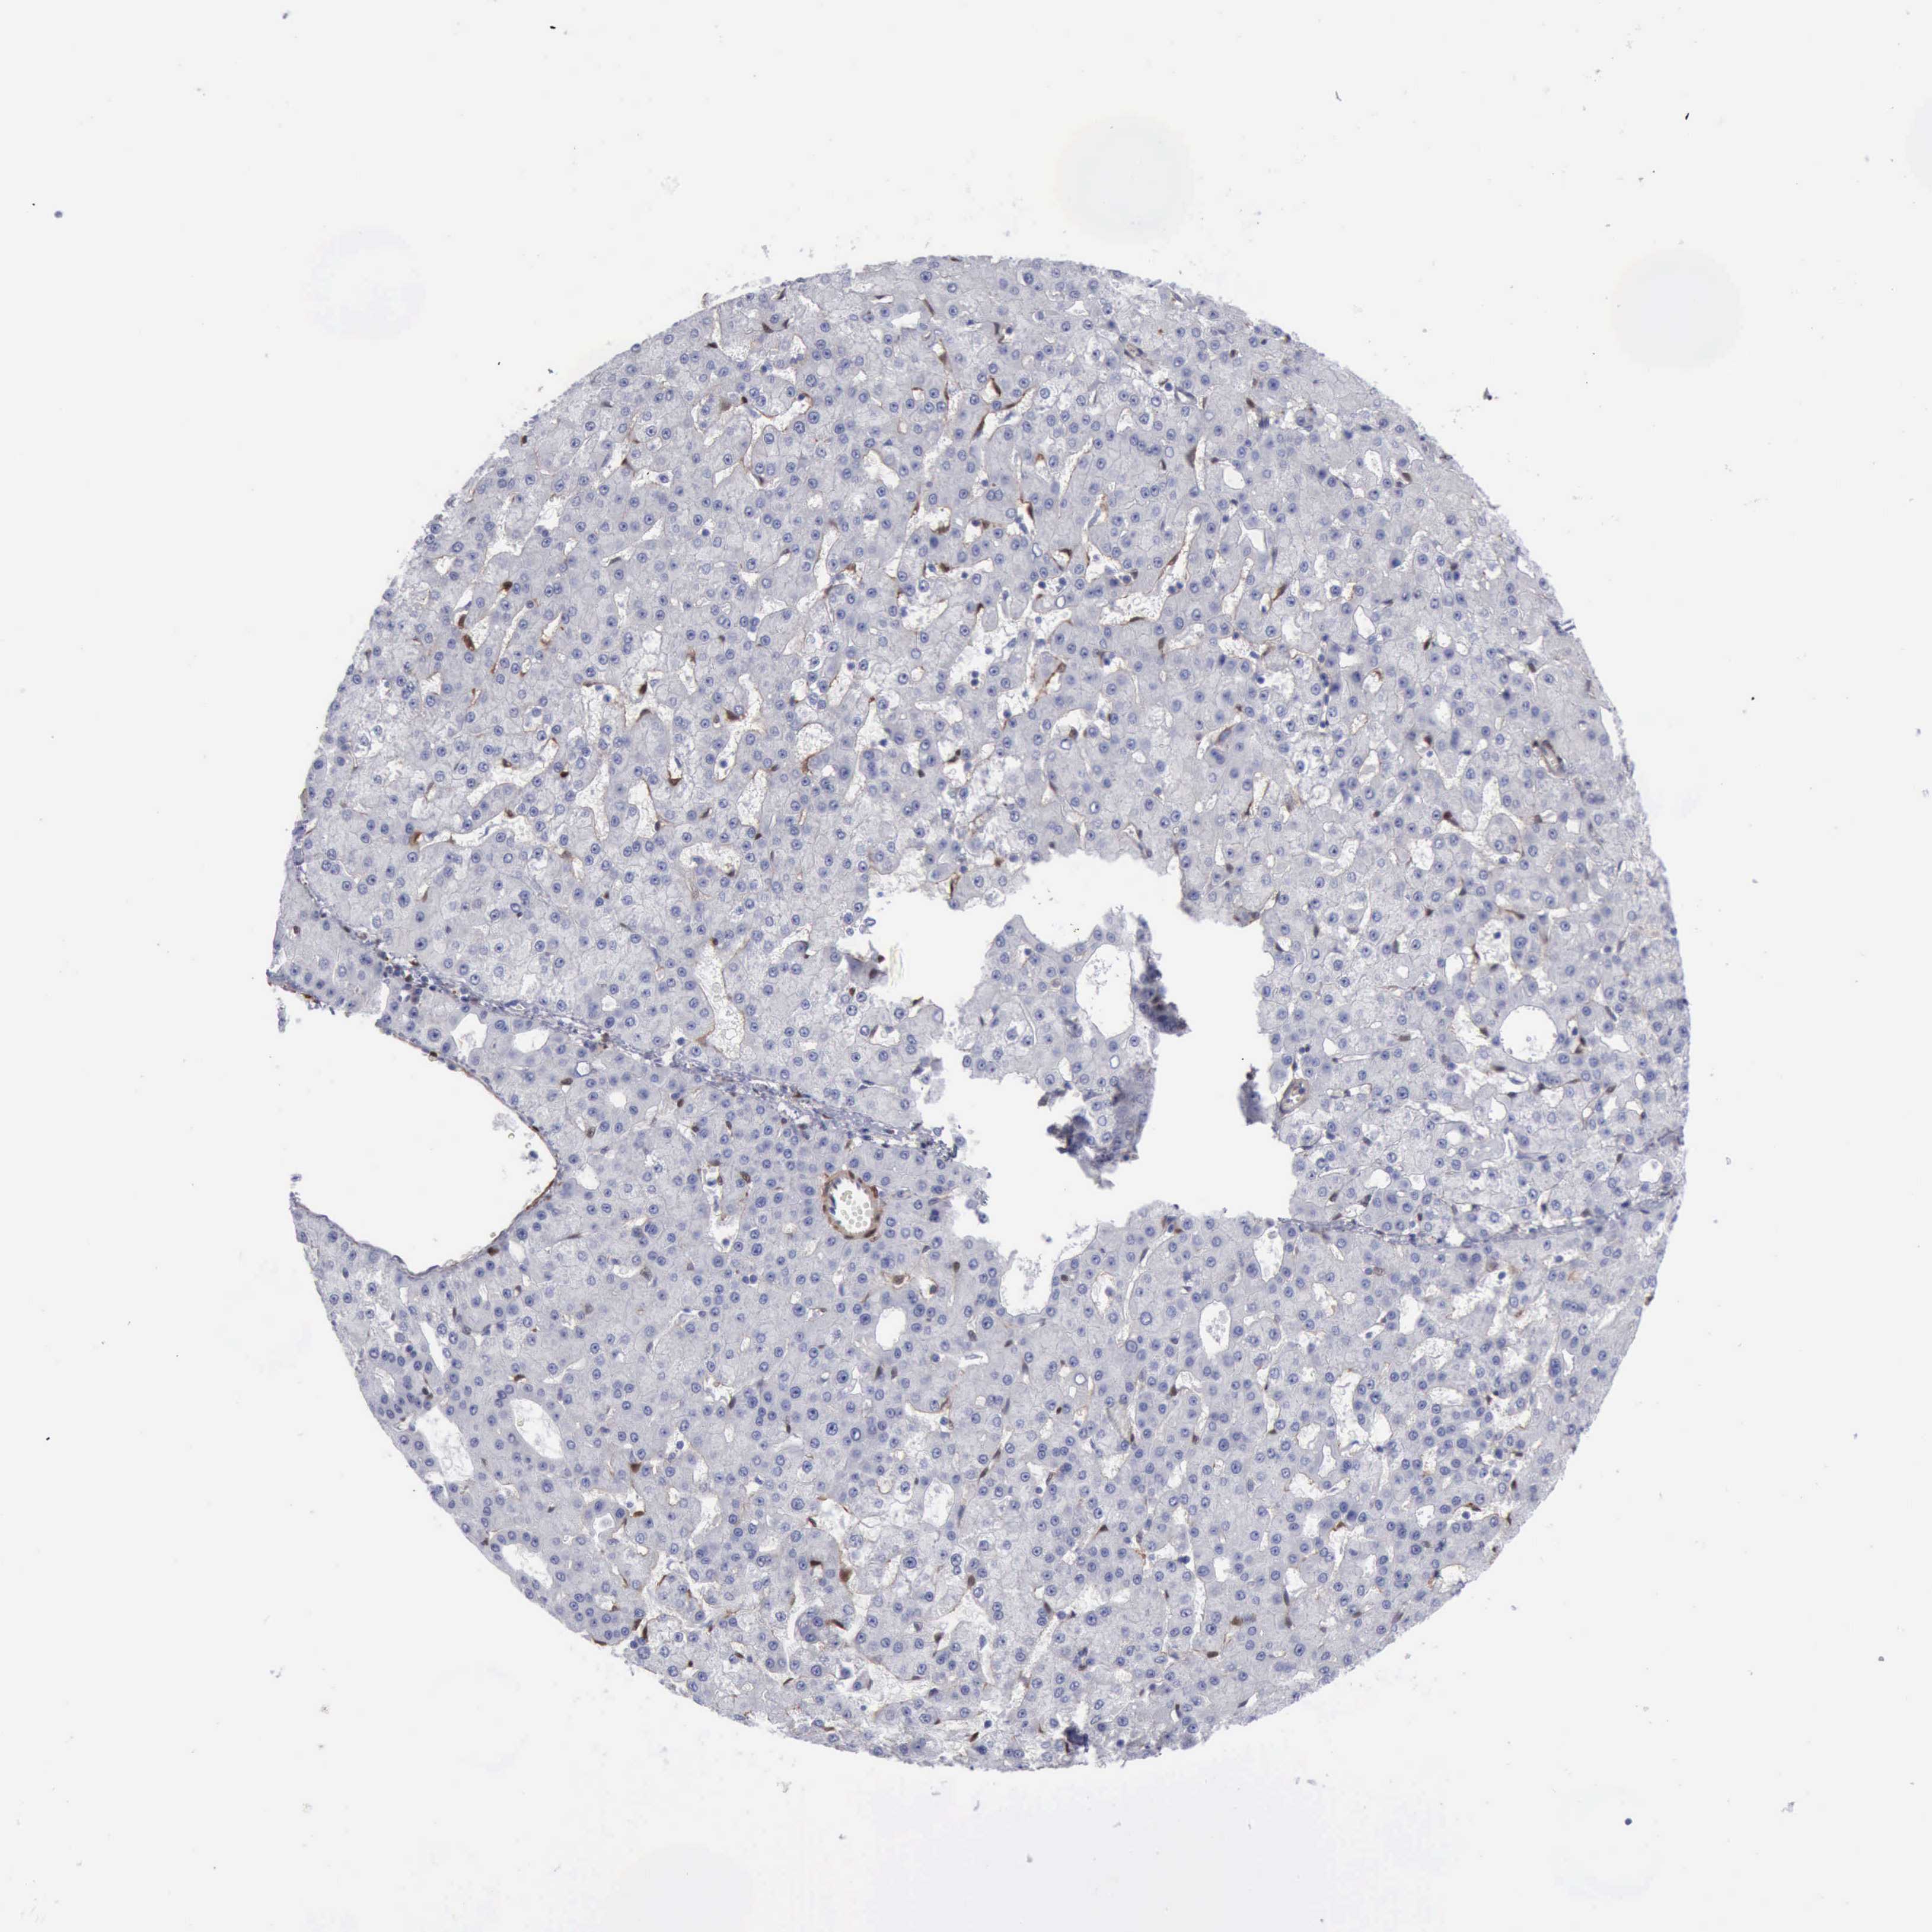

LIVER CANCER - Protein expressioni

A mouse-over function shows sample information and annotation data. Click on an image to view it in a full screen mode. Samples can be filtered based on level of antibody staining by selecting one or several of the following categories: high, medium, low and not detected. The assay and annotation is described here.

Note that samples used for immunohistochemistry by the Human Protein Atlas do not correspond to samples in the TCGA dataset.

Antibody stainingi

Antibody staining in the annotated cell types in the current human tissue is reported as not detected, low, medium, or high, based on conventional immunohistochemistry profiling in selected tissues. This score is based on the combination of the staining intensity and fraction of stained cells.

Each image is clickable and will lead to virtual microscopy that enables deeper exploration of all samples and also displays staining intensity scores, fraction scores and subcellular localization as well as patient and tissue information for each sample.

Antibody HPA001040

Antibody HPA001391

Antibody CAB020817

Staining

Carcinoma, Hepatocellular, NOS

Cholangiocarcinoma